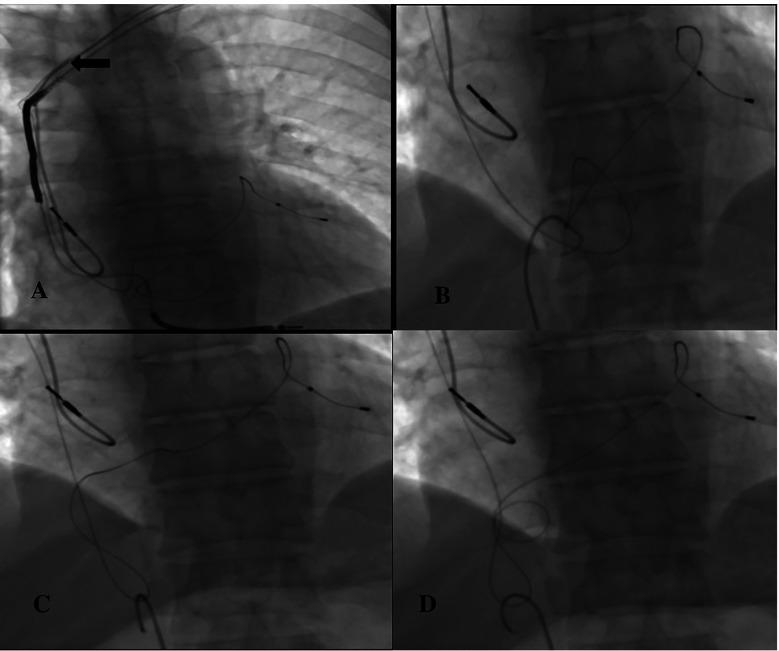

Entering through the right femoral vein and removing the coronary sinus lead with a pigtail catheter.

In our attempt to extract the coronary sinus lead, it fractured. The broken fragment was successfully removed without any complications.

In this case, which is very rarely encountered in daily practice, we successfully removed the coronary sinus lead from the body from the femoral vein using a pigtail catheter with a new method.

经右股静脉进入,用猪尾导管取出冠状静脉窦导线。

在试图取出冠状静脉窦导线时,导线发生断裂。断裂的碎片被成功取出,无任何并发症。

在日常实践中很少遇到这种情况,我们采用一种新方法,通过猪尾导管经股静脉成功地将冠状静脉窦导线从体内取出。